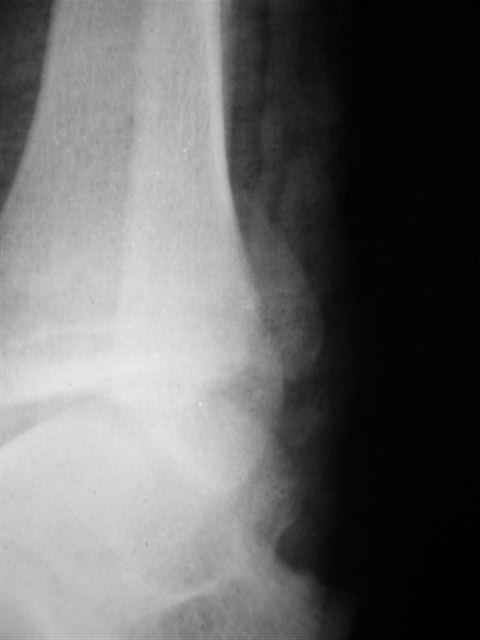

> интересуюсь тактикой лечения повреждений голеностопного сустава.

Я предупреждал, что ничего сверхъестественного. Каюсь, что одна из спиц прошла несколько дальше, чем нужно было, но главное - перелом стабилизирован и больной работает суставом в полном объёме, несмотря на представленную раннее травму коленного сустава.